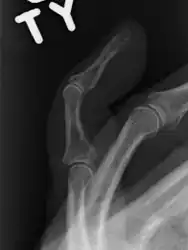

The diagnosis is generally based on symptoms and supported by X-rays.[3] The injury can be accompanied by swelling and ecchymosis.[6]

X-ray showing fracture at the insertion of the extensor tendon